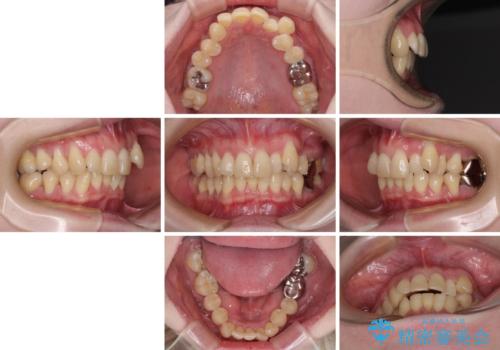

八重歯と先天欠損の歯列 ワイヤー矯正ですっきりと

- 八重歯と正中のズレを気にして来院された患者様です。

上顎左側が八重歯になっており、上顎正中が左側にずれていました。

上顎左側の第一小臼歯を抜歯し、補助装置を用いて正中位置を改善しながら八重歯を解消していくこととしました。

下顎前歯が1本欠損していたため、上下正中の位置が合わせるという目標はなく、鼻筋に上顎正中を合わせていくように移動を行いました。